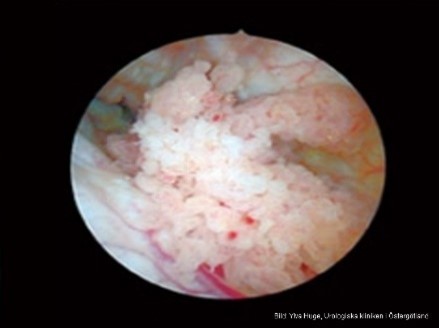

Vad ser du?

Förmodad urinblåsetumör